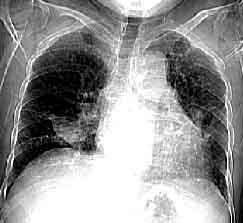

肺炎胸片呼吸道隔離由於支原體感染可造成小流行,且患兒病後排支原體的時間較長,可達1~2個月之外。嬰兒時期僅表現為上呼吸道感染症狀,在重複感染後才發生肺炎。同時在感染支原體期間容易再感染其它病毒,導致病情加重遷延不愈。因此,對患兒或有密切接觸史的小兒,應儘可能做到呼吸道隔離,以防止再感染和交叉感染。

肺炎患者胸片靜脈注射紅黴素乳糖酸鹽300mg,4min的血濃度平均為40.9μg/ml,2h後為2.6μg/ml,6h後為0.32μg/ml。如每12h連續靜脈滴注紅黴素乳糖酸鹽1g,則8h後的血藥濃度可維持4~6μg/ml。而痰中平均嘗試為2.6(0.9~8.4)μg/ml。紅黴素主要經膽汁排泄,部分可從腸道內重新吸收。相當量的紅黴素在肝內代謝滅活。